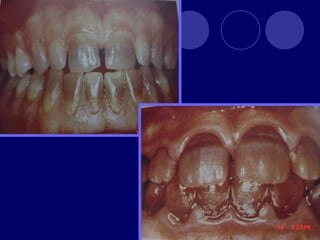

AMELOGENESIS IMPERFECTA  Hipoplásico: Zonas ausentes de esmalte  Afecta más a caras vestibulares  Esmalte: blanco amarillento y marrón claro, consistencia dura, fosas y surcos oscuras, delgado  Hipocalcificado:  Cualitativo  Esmalte frágil, fácil de desprender  Rx: falta de contacto entre dentina, esmalte  Hipomaduro:  Disminución en el contenido mineral  Esmalte blando y rugoso, veteado de blanco a marrón (esmalte en copos de nieve)  Más frecuente en caras vestibulares y dientes superiores

DISPLASIA AMBIENTAL DEL ESMALTE HIPOPLASIA POR INGESTA DE FLÚOR: fluorosis, manchas opacas, esmalte sin brillo(leve=lechoso, graves=amarillo/café) .

DENTINOGENESIS IMPERFECTA TIPO I:asociada a padecimiento esquelético, asociada a osteogénesis imperfecta (escleróticas azules, sordera, múltiples fracturas,etc.)  Dos denticiones  Dientes blandos, consistencia terrosa  Rx: cámaras pulpares obliteradas

TIPO II:  Dientesde color: amarillo, pardo azulado u opalescente con brillo translúcido, raíces color ámbar  Rx: coronas bulbosas, cámaras pequeñas o ausentes, raíces delgadas y cortas TIPO III: (SHIELDS)  Temporal: translúcido, ámbar  Permanente: normal